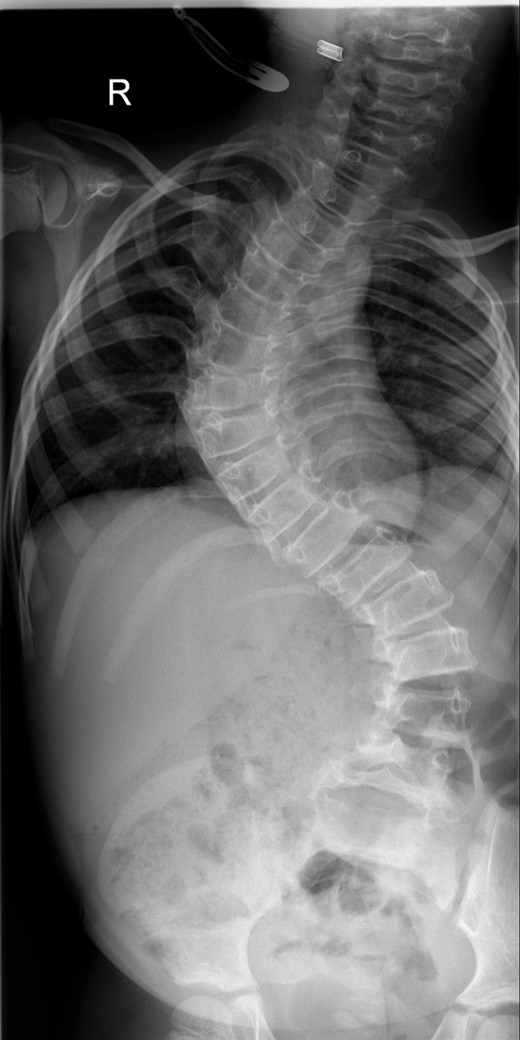

Between the ages of 4 and 6 years, the curve increased rapidly leading to a significant curve measuring 80° in the thoracic spine and 65° in the thoracolumbar spine with a T1–S1 height of 232 mm and T1–T12 height of 150 mm (Fig. 1). A decision was made to intervene operatively and posterior instrumentation with MCGR was performed. Special consideration was given to her bone fragility. Following 4.5 years of bisphosphonate therapy, her last bone mineral density (BMD) assessment by dual energy X-ray absorptiometry before surgery was normal. Her lumbar spine BMD Z-score was +1.5 and the total body less head BMD Z-score was also +1.5. Thus, at age 6 years, a construct of three paired sets of pedicle screws were placed at L2–L4 distally and a combination of pedicle screws at two levels (T4 and T5), with an outer square of sublaminar bands passed under the third and sixth ribs, was placed proximally. The instrumentation used was a 4.5 Expedium System (DePuy Synthes, Raynham, MA, USA) and the Silc Sublaminar Banding System (Globus Medical, Audubon, PA, USA). Post-operative radiographs (Fig. 2) showed good spinal balance and correction of deformity, but fractures of the right 5th and 10th ribs were seen posteriorly at the junction of the rib and transverse process. Following 8 weeks of spinal cast jacket protection, a CT scan showed the rib fractures to have healed. After instrumentation the thoracic curve angle measured 38° and the thoracolumbar curve measured 30°, with a T1–S1 height of 247 mm and a T1–T12 height of 160 mm.

An immediate post-operative whole spine radiograph demonstrating the spinal construct with the MCGR rods (measuring 38° in the thoracic curve and 30° the thoracolumbar curve with a T1–S1 height of 247 mm and a T1–T12 height of 160 mm).